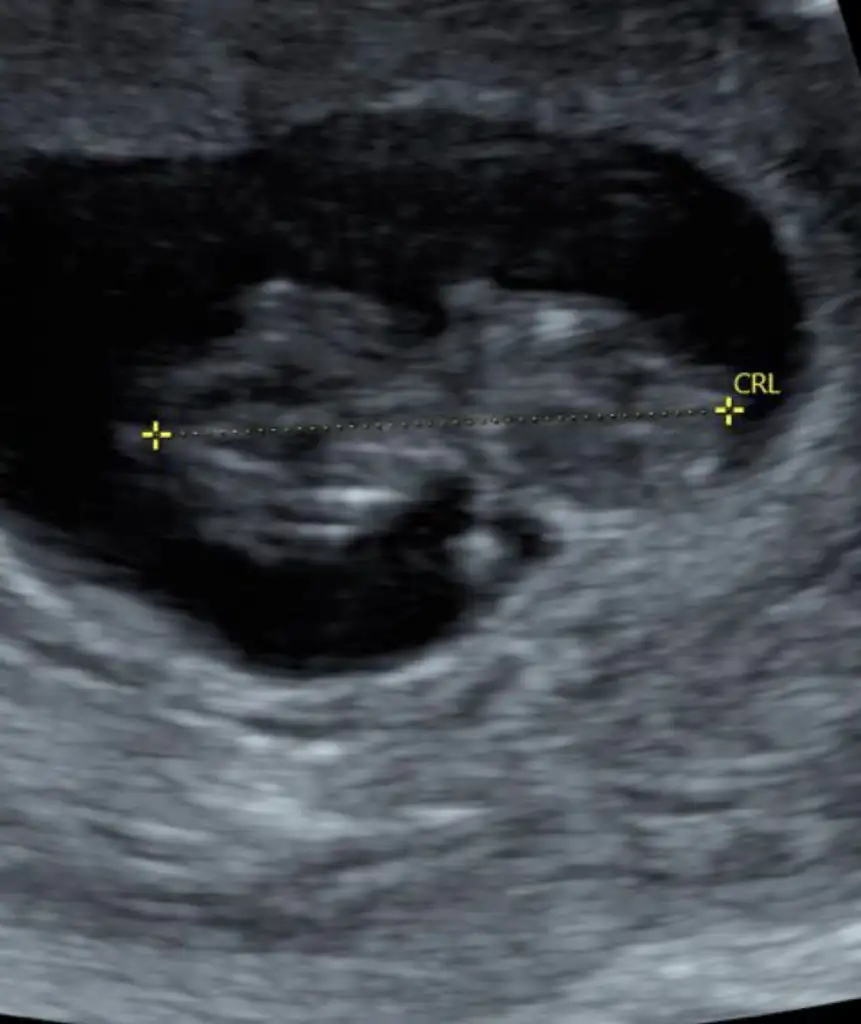

11. Haftamız yakında bitecek benımki böyle poz verdi sence ?

Şimdilik kız yönünde tabiki en iyi 12-13 hafta olursa paylasin11. Haftamız yakında bitecek benımki böyle poz verdi sence ?